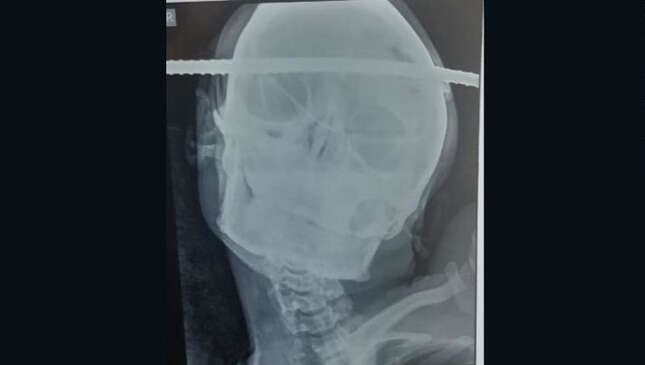

Tal y como cuentan varios medios hoy, Bahe se encontraba en medio de un trabajo de reparación en una obra de construcción cuando accidentalmente cayó en un pozo. Un accidente de una fracción de segundo que terminó con una gran barra de hierro incrustada directamente a través de su cabeza, de lado a lado.

Al parecer, después de que lo trasladaran al Hospital B.J., en la ciudad de Gondia, los médicos pudieron retirarle cuidadosamente la barra y evaluar el daño. Lo que encontraron fue ciertamente impactante. El diagnóstico encontró que la barra había ingresado en el cráneo a través de la región temporal derecha de su cerebro, y que había salido a través de la región frontal izquierda, sin embargo, de alguna forma el pedazo de metal había evitado atravesar zonas que le causaran un daño irreversible.